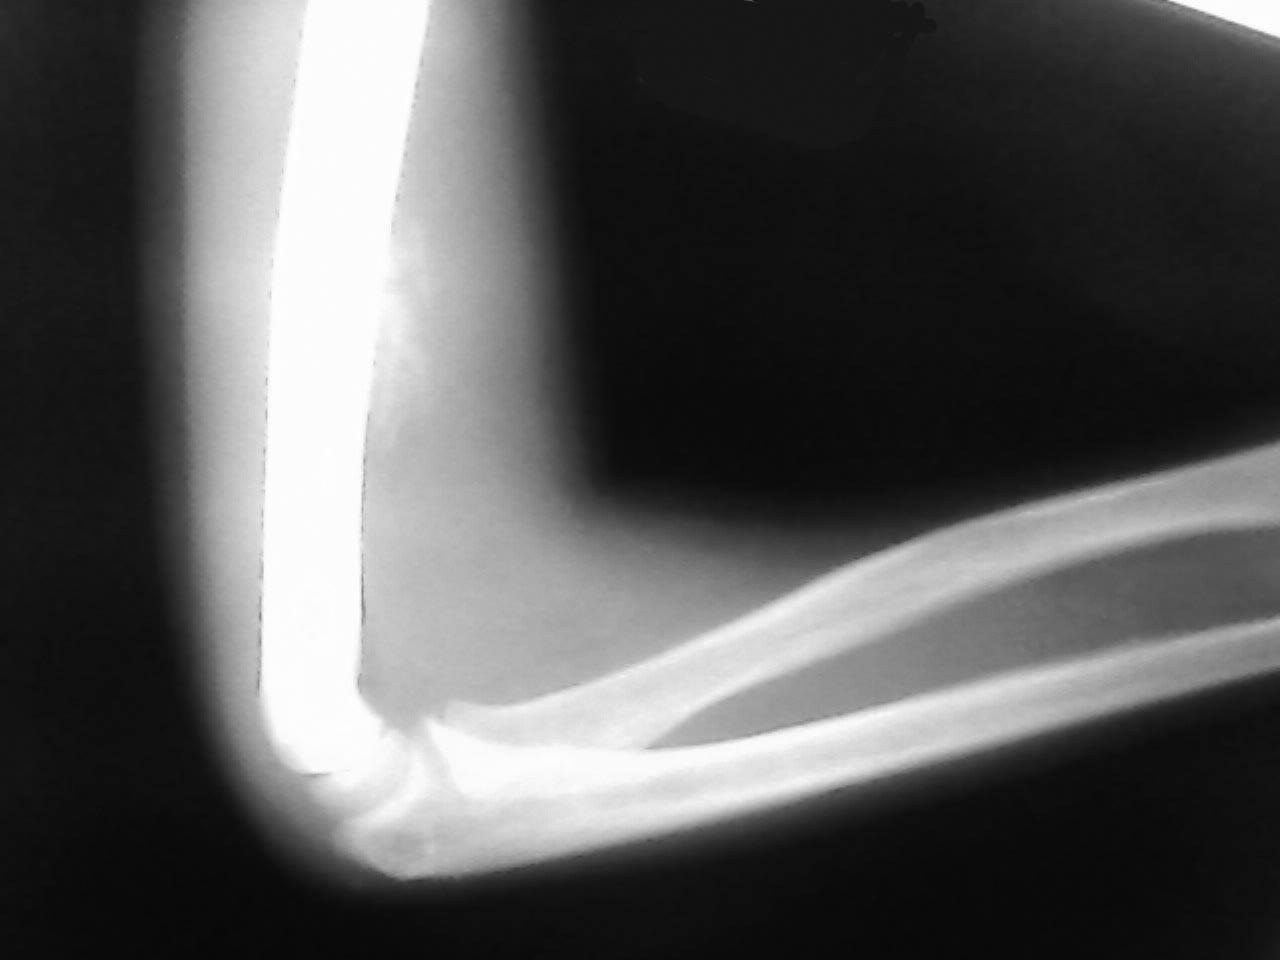

Добрый день, уважаемые коллеги! Поступил ребёнок 12 лет с явлениями

сгибательной контрактуры правого локтевого сустава.

В анамнезе около 2-х месяцев назад травма при падении с высоты роста на

обл.прав.плеча. Ребёнок из малообеспеченной многодетной семьи из

глубинки, за мед.помощью не обращался. Со временем появились тянущие

боли в плече и явления контрактуры. Сгибание возможно, разгибание до

угла 90. Отёка плеча нет. Кожные покровы в проекции плеча без

особенностей, сосудистых и неврологических нарушений не выявлено.

Предположительный диагноз : Посттравматический гетеротопический

оссификат правого плеча. Сгибательная контрактура правого локтевого сустава.

Вопросы: какая тактика обследования и лечения? Прошу извинения за

качество снимка. Если причина данного состояния действит.гетеротопич.

оссификат что в плане лечения? Кроме НПВП, фонофореза гидрокортизона,

э/фореза лидазы, магнитотерапии, дозированной ЛФК, вариантов пока нет...

Судя по снимку процесс оссификации не завершился. Редрессировать в таких

случаях вроде нельзя... Хотелось бы услышать мнение и рекомендации

сообщества по тактике обследования, лечения, ссылки на лит-ру.